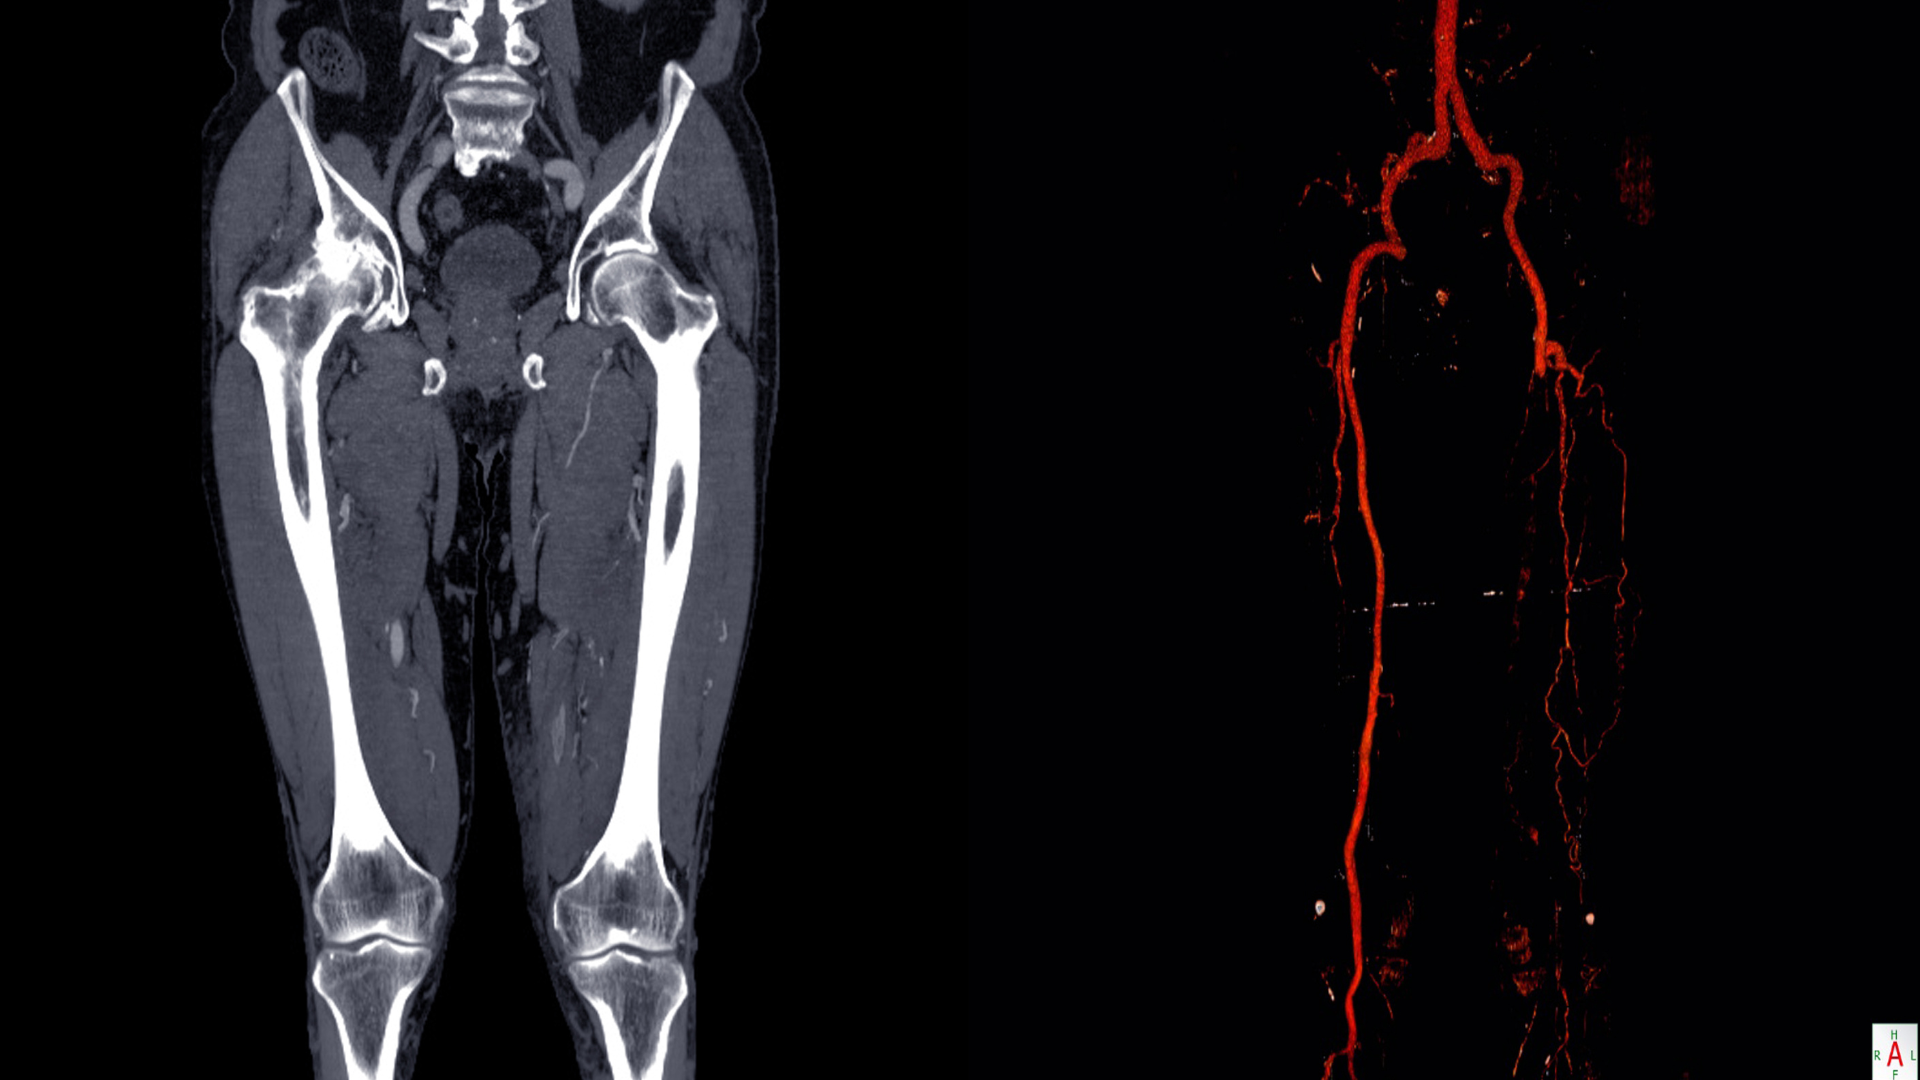

Chẩn đoán bệnh lý tĩnh mạch hiển lớn

Để xác định chính xác tình trạng, bác sĩ sẽ khai thác triệu chứng và thực hiện các xét nghiệm hình ảnh. Phương pháp được dùng phổ biến nhất là siêu âm Doppler tĩnh mạch chi dưới, cho phép quan sát dòng chảy, kiểm tra sự hiện diện của huyết khối, mức độ trào ngược và hoạt động của van tĩnh mạch.

Trong các trường hợp phức tạp hoặc cần đánh giá toàn bộ hệ mạch, có thể chỉ định thêm:

- Chụp CT tĩnh mạch (CT venography) để xác định vùng hẹp hoặc tắc.

- Chụp MRI mạch máu nhằm đánh giá mô mềm xung quanh.

- Xét nghiệm máu (nếu nghi ngờ rối loạn đông máu).

Kết quả giúp định hướng phương án điều trị phù hợp: Điều trị bảo tồn, can thiệp nội mạch hoặc phẫu thuật.